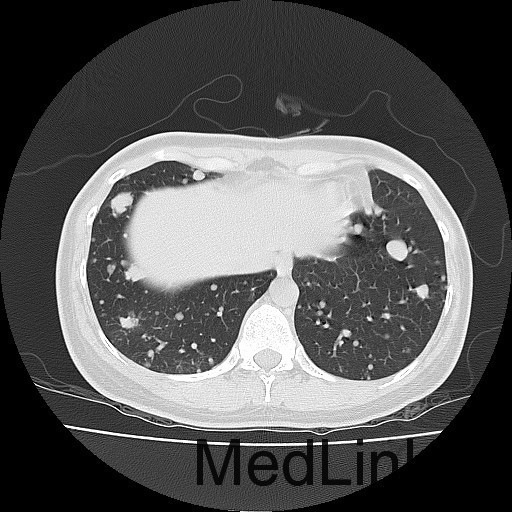

查体:右大腿上段较左侧增粗,后内侧皮下可触及大小约5*6cm肿物,质软,边界不清,活动度可,压痛(+),无波动感。 辅助检查:胸部CT:双肺多发转移瘤。

诊断:肺占位性病变(转移瘤?);大腿软组织疾患(右侧大腿肿物) 治疗:入院右下肢MR平扫+增强扫描:右侧大收肌软组织占位性病变,考虑间叶源性恶性肿瘤可能性大,血管源性可能?瘤周多发静脉曲张及侧枝循环形成,建议CT增强扫描进一步检查明确血管情况。遂于声引导下右大腿肿物穿刺活检,病理结果提示:(右大腿肿物)送检穿刺组织,肿瘤细胞形成器官样及腺泡状结构,细胞巢间为纤维性分隔,细胞呈大圆形、多边形,胞质丰富透亮,部分呈嗜伊红色,细胞核大,核分裂象少见,结合临床病史及免疫组化,考虑为腺泡状软组织肉瘤。免疫组化结果(①):CK(-),Vim(-),Ki-67(5%+),HMB45(-),MelanA(-),SMA(+),desmin(-),Myogenin(-),MyoD1(-),S100(-),NSE(部分+),CD56(-)。